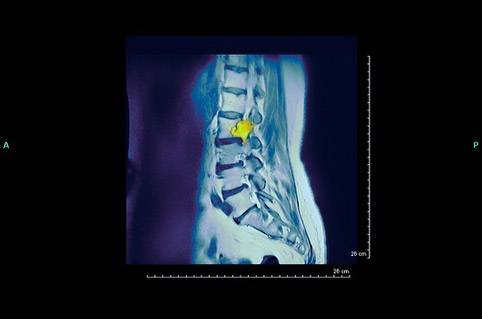

Опухоли поясничного отдела

При сдавлении спинного мозга на уровне поясничного отдела позвоночника возникают:

- нарушения функции тазовых органов (расстройства мочеиспускания, дефекации, непроизвольные физиологические отправления, эректильные дисфункции у мужчин);

- снижение чувствительности и возникноаение парестезий (ощущение покалывания, ползания мурашек) в нижних конечностях.

При прогрессировании сдавления контроль над дефекацией и мочеиспусканием теряется полностью, развивается паралич в ногах, чувствительность отсутствует.

Фото: опухоль поясничного отдела позвоночника

Рост опухоли со сдавлением спинномозговых корешков в поясничном отделе сопровождается симптомами, напоминающими клинику люмбаго (пояснично-крестцового радикулита):

- резкие боли в спине с периодическими прострелами в ягодицу, бедро;

- возможны парестезии, изменение цвета и температуры ноги со стороны поражения (становится холодной на ощупь, появляется синюшность или мраморность кожи).